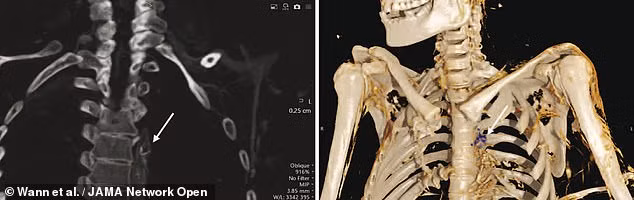

(Kiến Thức) - Các chuyên gia mới tiến hành loạt kiểm tra đới với các xác ướp 500 tuổi của người Inuit và có những phát hiện bất ngờ về sức khỏe của họ. Kết quả nghiên cứu cho thấy họ có chế độ ăn giàu axit béo omega-3 nhưng vẫn bị tắc nghẽn động mạch.

Mới đây, các chuyên gia công bố kết quả nghiên cứu đáng chú ý về những xác ướp của người Inuit. Do xác ướp được bảo quản cực kỳ tốt nên các chuyên gia gặp một số thuận lợi trong việc nghiên cứu.

Cụ thể, kết quả nghiên cứu mới cho thấy người Inuit sống cách đây khoảng 500 năm có chế độ ăn giàu axit béo omega-3.

Dù có chế độ ăn giàu axit béo omega-3 nhưng những người Inuit trên vẫn bị tắc nghẽn động mạch.